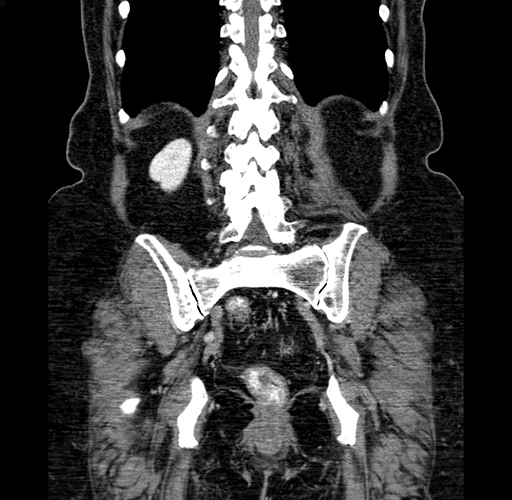

Pre-Chemo: Coronal Venous

Coronal Venous